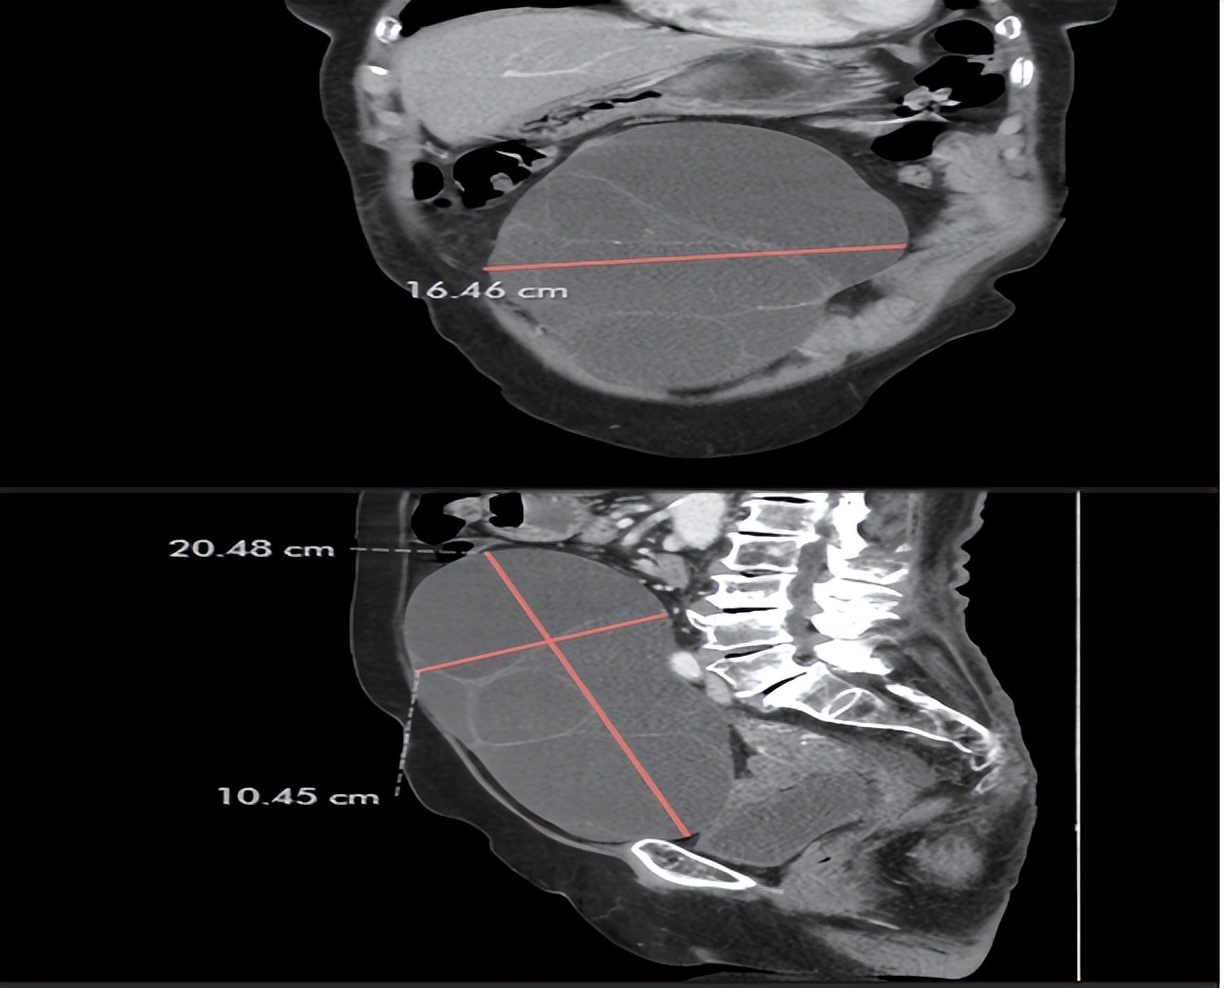

今年年初,患者因反复腹胀至医院检查发现腹部巨大肿瘤。后转至乔治敦公立医院进一步诊疗,查CT提示盆腔内巨大肿瘤大小20.4cmx16.4cmx10.45cm,相当于怀孕足月胎儿大小。当地医生计划实施开腹手术,但手术后会留有20cm的切口,创伤大。江源主任和医疗队影像科主任窦鑫一起会诊阅片后,分析认为患者虽然肿瘤巨大,但是其内部为囊液,可以进行单孔腹腔镜手术,先行吸除囊液,缩小肿瘤后进行卵巢切除,最大限度减少手术创伤。为了患者的后期快速恢复,江源主任与当地医生沟通后,决定采用经脐单孔腹腔镜下卵巢切除术。手术的切口选择了人体天然的皱襞——脐部,长度约2.5cm,吸除囊液约5000ml,成功的将该囊肿及卵巢切除。